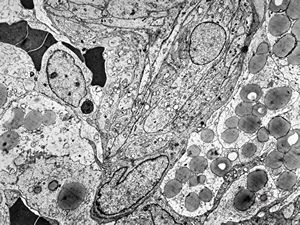

rabbit spinal cord trauma

rabbit spinal cord trauma